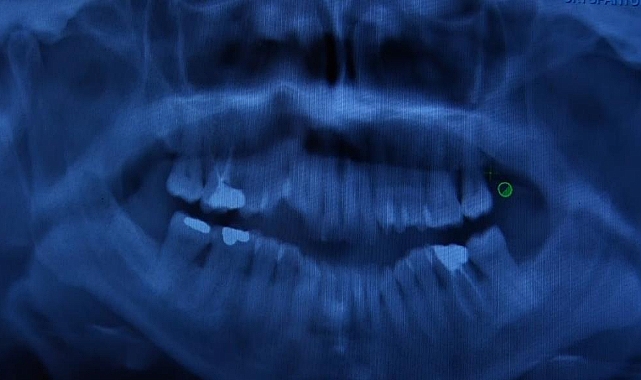

Uzm. Dt. Ebru Özkan Bütün, "Sağlıklı dişler sağlıklı bir zemin üzerinde var olabiliyor. Diş eti rahatsızlıkları genelde sessiz ilerler. Bize hastalar bir ağrı şikayetiyle değil de daha çok diş etlerinde kanama, diş sallanması ya da diş eti çekilmesi olduğu zamanlarda başvurur. Hatta randevularımızın çoğunu başka diş hekimlerinin yönlendirmesiyle durumun farkına varan hastalar oluşturmakta. Oysa bahsettiğim başvuru nedeni olan o şikayetler hastalığın ileri aşamalarını gösteriyor. Bu nedenle erken teşhis ve tedavi koymak için rutin kontroller diş hekimliğinde çok önemli. Tedavi süreci kişiye özel bizde basit bir diş taşı temizliğiyle de sorunu çözebiliyoruz ama bu ileri cerrahi aşamalara kadar da ilerleyebiliyor. En önemli nokta; kişinin evde uyguladığı ağız hijyeni uygulamaları, rutini. Her zaman söylüyoruz; günde en az 2 kere diş fırçalama, diş ipi kullanımı veya ara yüz fırçası kullanımı, düzenli kontrolleri aksatmamak altın standart. Bunlara uyulduğu sürece durum da kontrol altında olacaktır" dedi.

Sık yapılan hatalara yönelik konuşan Dt. Bütün, "Çok sık karşılaştığımız bir durum var; hastalar diş eti kanadığında fazlaca bastırdım sanarak fırçalamayı azaltıyorlar ya da daha yumuşak fırçalara geçerek yetersiz fırçalamaya başlıyorlar oysaki durum bunun tam tersi. Diş etlerimizin kanaması o bölgeye fırçayı daha çok sürmemiz ve daha etkili temizlememiz için gelen bir sinyaldir. Eğer dişlerimiz kanıyorsa direkt diş hekimimize müracaat etmeliyiz. Periodontal sağlık vücudumuzun genel olarak bütünüyle de ilişkilidir sadece ağzı için önemli değildir. Artık biliyoruz ki diyabetten kalp damar rahatsızlıklarına ya bazı solunum yolu hastalıklarından nörolojik rahatsızlıklara kadar pek çok sistemle ilişkili bulunmuş bu periodontal durumlar. Diş eti kanamaları bazı hastalıkların göstergesi olabiliyor. ‘Kaplama yaptırdım o yüzden fırçalamıyorum’ olayı var. Kişi, dişler kaplandığı için onları temizlemeyeceğini düşünüyor aksine araları daha iyi temizlemeliyiz, normal dişlere sahip bir bireydense kaplamalı dişlere sahip bireyler ara yüz temizliğine çok önem vermeli, gerekirse ağız duşu uygulamalı. Kaplamalı dişler ya da ağızda ilave bir şeyleri; aparey, tel varsa onların da dikkat etmesi gerekiyor. Yaş sınırı tok, genel olarak ağız bakımı yetersizse ve bu temel oluşmuşsa kanama, diş eti rahatsızlıkları ve kemik kaybına kadar ilerleyen şeyler gördüğümüz bir şey" şeklinde konuştu.